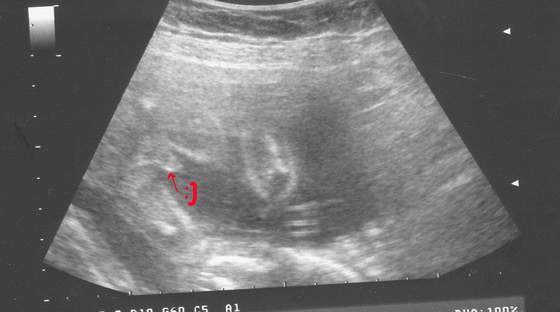

czuje czkawke!!!! ale śmieszne uczucie

Lenuske szarpie że hej....pewnie po frytach co się matka napchała